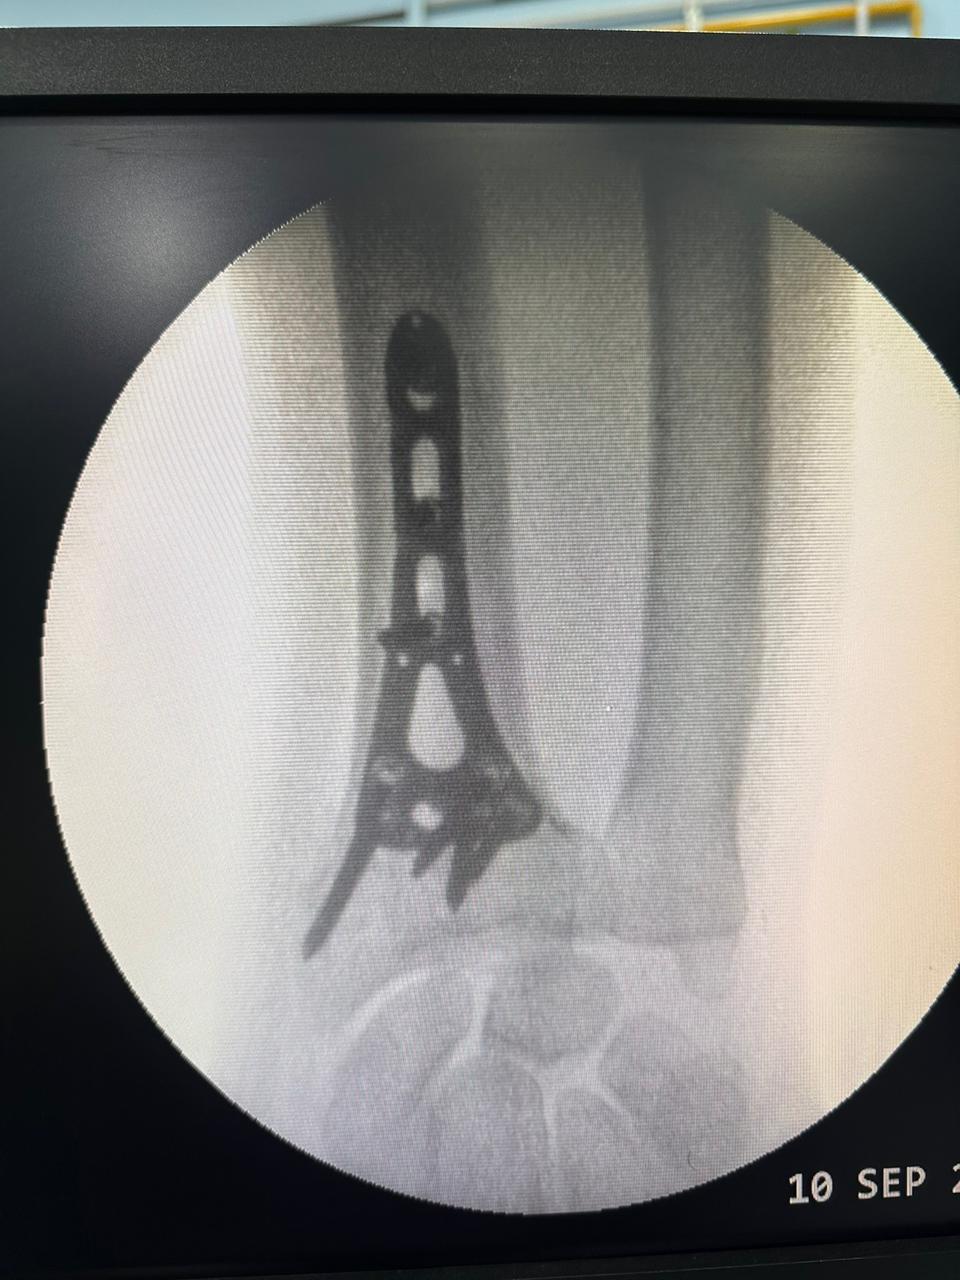

Moments That Mark Meaningful Recovery

Witness real patient transformations at The Ortho Clinic through images that reflect successful treatments and restored mobility.